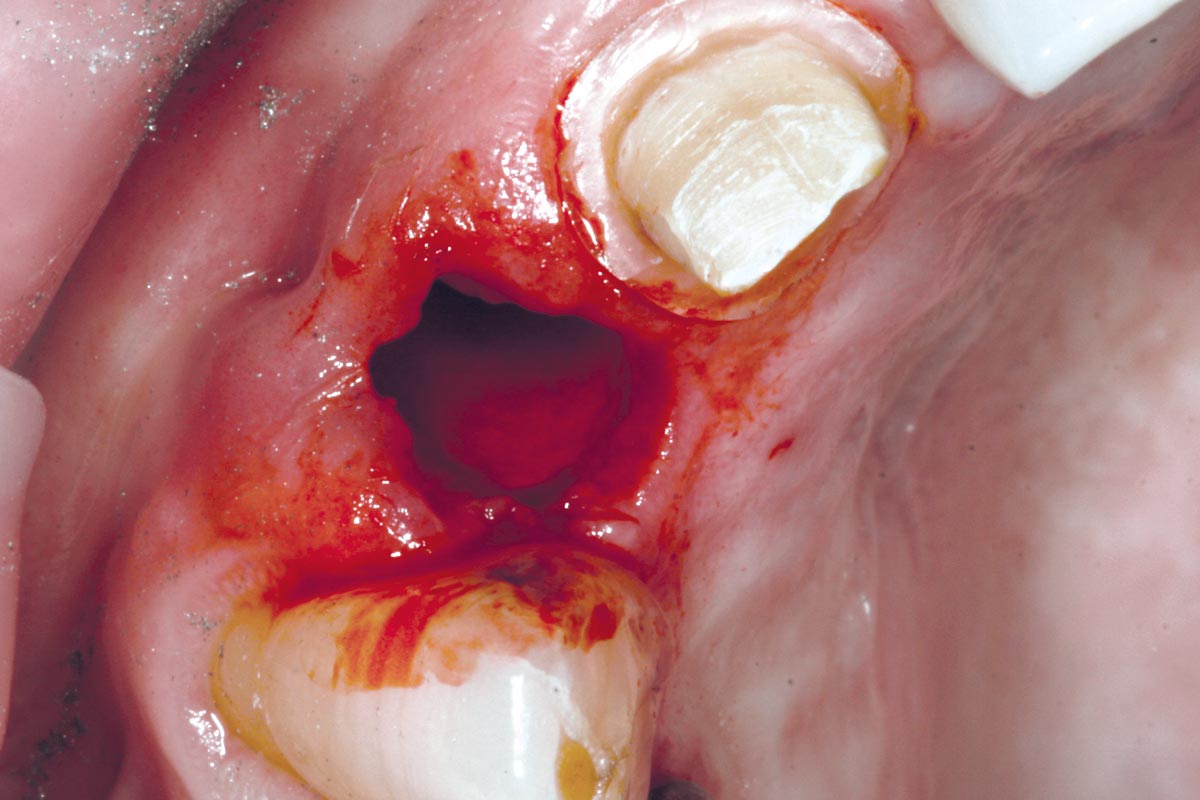

3/19 - Fracture of tooth while extractionBone augementation with maxresorb® - Dr. R. Cutts